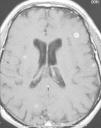

Meningitis con múltiples lesiones intracraneales

R. Fernández-Rodrígueza, P. Prieto Casalb, R. Gómez Fernándeza, J. Pérez-Cidb, M. Bustillo Casadoa

a Servicio de Medicina Interna-Enfermedades Infecciosas.

b Servicio de Radiología. Hospital Cristal. Complexo Hospitalario de Ourense. Ourense.